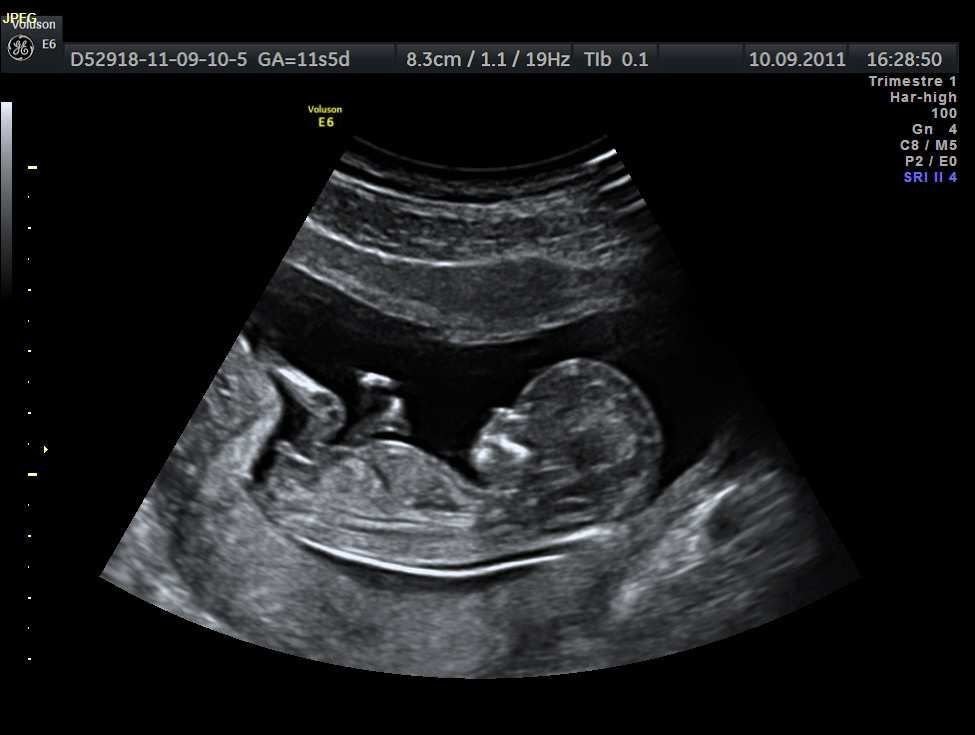

Another area of scientific focus involves prenatal environmental factors that may influence neurodevelopment. Researchers are examining how conditions during pregnancy—such as maternal health, nutrition, and exposure to certain environmental elements—may interact with genetic predispositions.

Studies suggest that prenatal environments play a role in shaping how the developing brain responds to growth signals. This does not imply direct causation, but rather a complex interaction between biological systems and environmental conditions. Factors such as inflammation, stress regulation, and metabolic balance during pregnancy are being explored for their potential influence on early brain organization.

One of the most consistently discussed areas in autism research focuses on timing during early brain development. Scientists suggest that autism may not arise from a single event, but rather from subtle changes occurring during critical windows of brain formation. During pregnancy and early infancy, the brain undergoes rapid growth, forming billions of neural connections that influence communication, sensory processing, and social behavior.

Research indicates that when this delicate timing is altered—due to genetic variations, biological signals, or environmental influences—the structure and function of neural networks may develop differently. This does not imply damage or deficiency, but rather variation in neurological wiring, which may contribute to traits associated with autism.

Scientists emphasize that these timing differences may affect how brain regions communicate with each other, potentially explaining differences in information processing, sensory sensitivity, or social interaction. Importantly, this research highlights autism as a developmental difference, not a disease or condition caused by a single harmful factor.